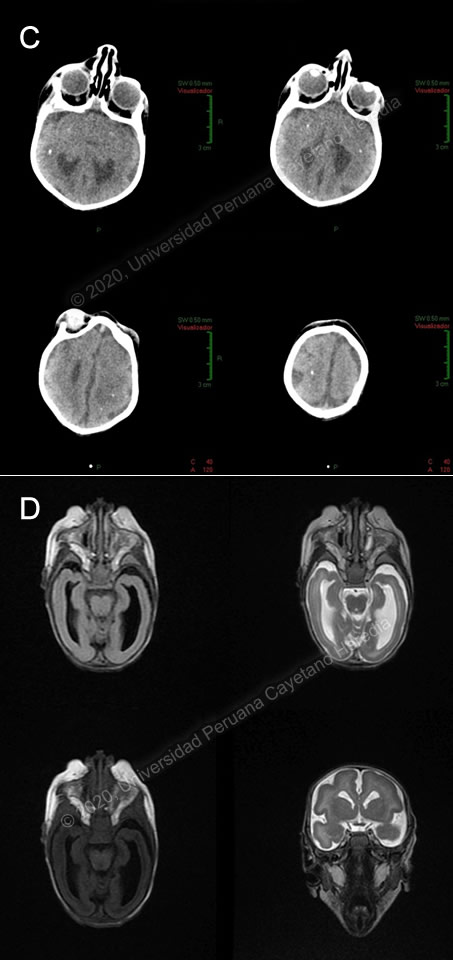

![]() Discussion: RT-PCR for Zika virus for the mother came back positive and close monitoring of her pregnancy ensued. Zika PCR and serology for the newborn was unavailable. A brain CT revealed microcephaly, bilateral calcifications of basal ganglia and frontal white matter, pachy-polymicrogyria in both hemispheres, and ventriculomegaly (Image C). Brain MRI showed bilateral frontal pachygyria, temporal, parietal and occipital bilateral lissencephaly, and dysplasia of the corpus callosum (Image D). Zika virus is flavivirus transmitted by mosquitoes, most commonly Aedes aegypti. It is closely related to other flaviviruses such as dengue, yellow fever and West Nile virus. Although it was first isolated in 1947, the first major outbreak occurred in 2007 in Micronesia, with an estimated 5000 infections among a population of 6700. By 2014, the virus had made its way to Latin America and after five years the largest number of cases were reported in Brazil (231,725), Colombia (98,803) and Venezuela (60,146) (PAHO/WHO). The first cases of Zika virus in Peru were reported in 2016 in the regions of Cajamarca and Loreto; last year, during the patient’s mother’s pregnancy, there was an active outbreak in the city of Jaen from February to August with a cumulative incidence of 1869 cases. Congenital transmission of Zika virus can occur at any moment during pregnancy and even peripartum, but the highest risk for fetal sequelae occurs with first and second-trimester infections. Following maternal infection, the virus is believed to infect the placenta and migrate to the fetal brain, where it causes apoptosis of neural progenitor cells (Curr Opin Virol, doi:10.1016/j.coviro.2017.09.005). Acute Zika virus infection presents with non-specific symptoms including maculopapular pruritic rash, fever, arthralgia, conjunctivitis, myalgia, and headache. It has been strongly associated with Guillain-Barré syndrome (N Engl J Med, doi: 10.1056/NEJMra1602113). Congenital infection causes a wide range of clinical manifestations in the fetus. Fetal cranial morphology may be severely altered, with microcephaly, overlapping cranial sutures, and redundant scalp skin, with extreme craniofacial disproportion. Brain anomalies such as subcortical intracranial calcifications, increased fluid spaces, cortical thinning and abnormal gyral patterns, hypoplasia or absence of the corpus callosum, decreased myelination and cerebellar hypoplasia are frequently associated. Ocular abnormalities such as cataracts, intraocular calcifications, chorioretinal atrophy, and optic nerve anomalies have also been reported. Congenital musculoskeletal abnormalities such as arthrogryposis and clubfoot are commonly observed as well, probably due to affection of the corticospinal tract or motor neurons. Cardiac abnormalities have a reported prevalence of around 10%, and are usually not severe (PLOS Negl Trop Dis, doi: 10.1371/journal.pntd.0006362). Five to ten percent of pregnancies with documented Zika infection result in fetal loss (JAMA Pediatr, doi: 10.1001/jamapediatrics.2016.3982). In the case presented, the patient had evidence of significant musculoskeletal and neurological involvement, as evidenced in the physical exam and brain imaging. Diagnosis is made by detection of viral nucleic acid by PCR or of IgM antibodies by ELISA. Viremia is usually transient, though it may last longer in pregnant women with evidence of fetal congenital infection, so a negative PCR does not rule out the diagnosis. IgM is thought to appear as viremia fades, within the first week after symptom onset, and it typically persists for months. Serology may cross-react with other flavivirus such as dengue (N Engl J Med, doi: 10.1056/NEJMra1602113). There are no reliable tests for prenatal and antenatal diagnosis of congenital Zika virus infection, although in some cases the amniotic fluid or cord blood might have a positive PCR. The diagnosis is confirmed by positive serum, urine of cerebrospinal fluid PCR for Zika virus in the newborn, in samples collected within the first two days of life (MMWR Morb Mortal Wkly Rep, doi: 10.15585/mmwr.mm6641a1). The differential diagnosis for congenital Zika infection must include other congenital infections that may cause microcephaly such as rubella, cytomegalovirus or toxoplasmosis. Rubella typically presents with congenital glaucoma and pigmentary retinopathy. Cytomegalovirus presents with a periventricular pattern of intracranial calcifications, as opposed to the subcortical distribution in Zika infection. Toxoplasmosis usually presents with diffuse intracranial calcifications. Of note, congenital Zika infection does not present with hepatosplenomegaly nor skin lesions (Am J Public Health, doi: 10.2105/AJPH.2016.303115) Although these findings may help differentiate between different entities, the final diagnosis must be made with virologic studies. Non-infectious causes of congenital abnormalities must also be ruled out. Patients with suspicion of congenital Zika virus infection should have a head ultrasound and a comprehensive ophthalmologic exam during their first month of life, as per CDC recommendations. There is no specific treatment, but patients should receive supportive management for complications (MMWR Morb Mortal Wkly Rep, doi: 10.15585/mmwr.mm6641a1). Prevention centers on avoiding mosquito bites through usage of mosquito repellent, bed nets, and window screens, and applying permethrin on clothes. Pregnant women should not travel to endemic areas. There is no vaccine against Zika, although there are several candidates in clinical phase I/II trials (Cell Host Microbe, doi: 10.1016/j.chom.2018.05.021). Our patient is being followed up by a multidisciplinary team comprised of pediatric neurologists, cardiologists, orthopedic surgeons, dietitians and, and undergoing physical therapy for hypertonicity. References: |